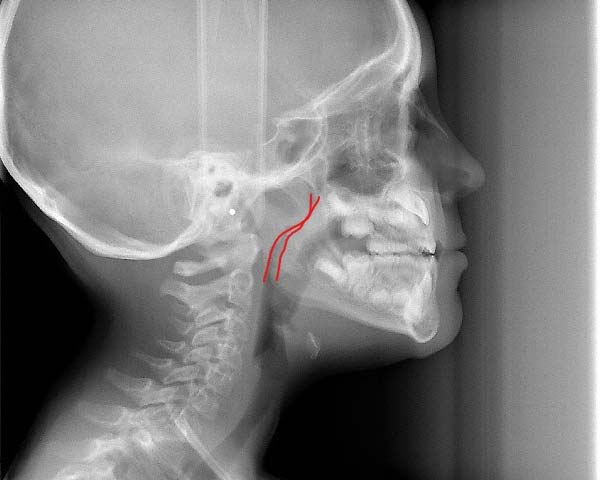

The best age is as soon as it is suspected there are airway issues, our youngest patient is 2.5 years old. The sooner we recognize an airway issue, the greater the chances of achieving harmonious physical and neural growth and development. Below are examples of patients in our practice who have undergone airway development for pediatric sleep apnea or sleep disordered breathing:Adults

We recognize many adults need expansion treatment but that becomes more difficult as we age. Adults with sleep disordered breathing present with many symptoms that can include, snoring, open mouth breathing, sleep apnea, upper respiratory resistance syndrome, and trouble falling or staying asleep. The goal is to determine why these symptoms are present and what can be done to improve the patient’s quality of life with appliances or surgical recommendations. Dr. Kuhta uses specialized bone supported expanders to change the shape of the jaw and not just mask the problem. Every treatment plan is specialized to your needs and aims to alter the way in which you breathe. Dr. Kuhta offer’s non-surgical and minimally invasive surgical options to expand or widen the upper jaw. Using bone-based expanders the goal is to widen the jaw and not just tip the teeth. By expanding the jaw with TAD-based (or mini implant) expanders, you can improve airway, increase room for the tongue, open the nasal cavity and correct crossbites. Skeletal expansion on adults can be life changing! If you are interested in the maxillary skeletal expander (MSE) your next step is scheduling an airway consultation. From there we determine if you are a possible candidate and progress to 3-D imaging to evaluate the probable success of expansion. Before your appointment if you would like to research MSE appliances, Dr. Kuhta would be happy to answer any specific questions.